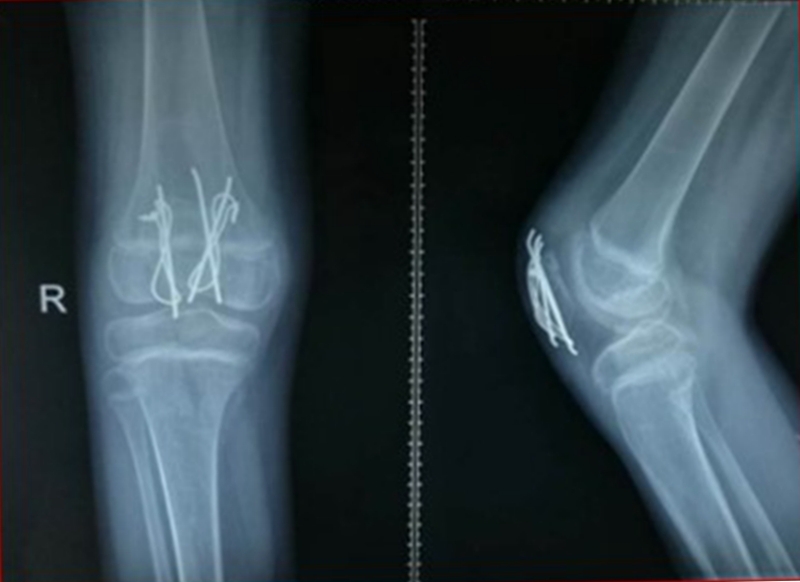

图1 受伤当时X线片

图2 受伤3周X线片